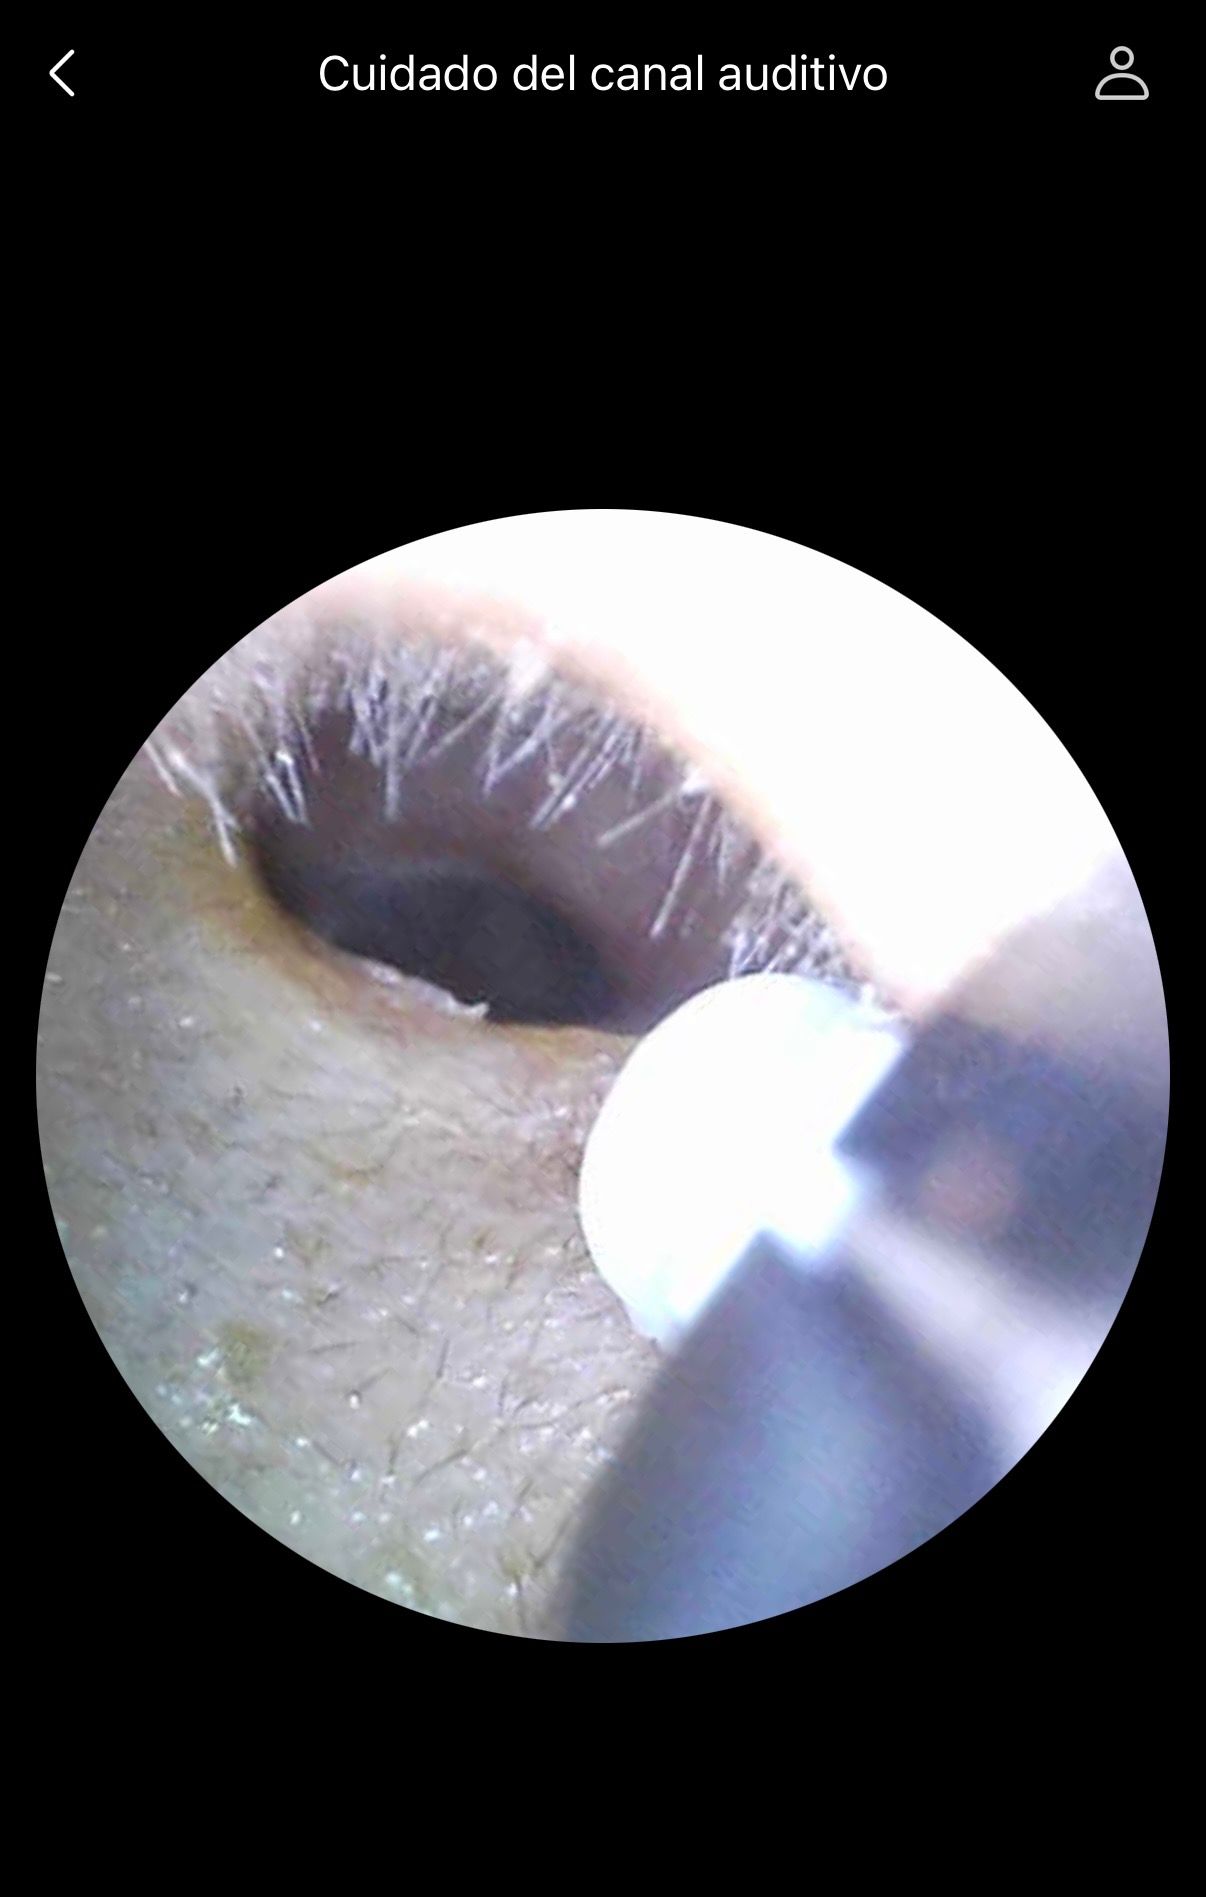

LAVADO DE OIDOS / LAVADO OTICO 650 MXN

Excelente atención del Dr. , y equipo muy bueno para la revisión y diagnóstico de mi problema de oído.